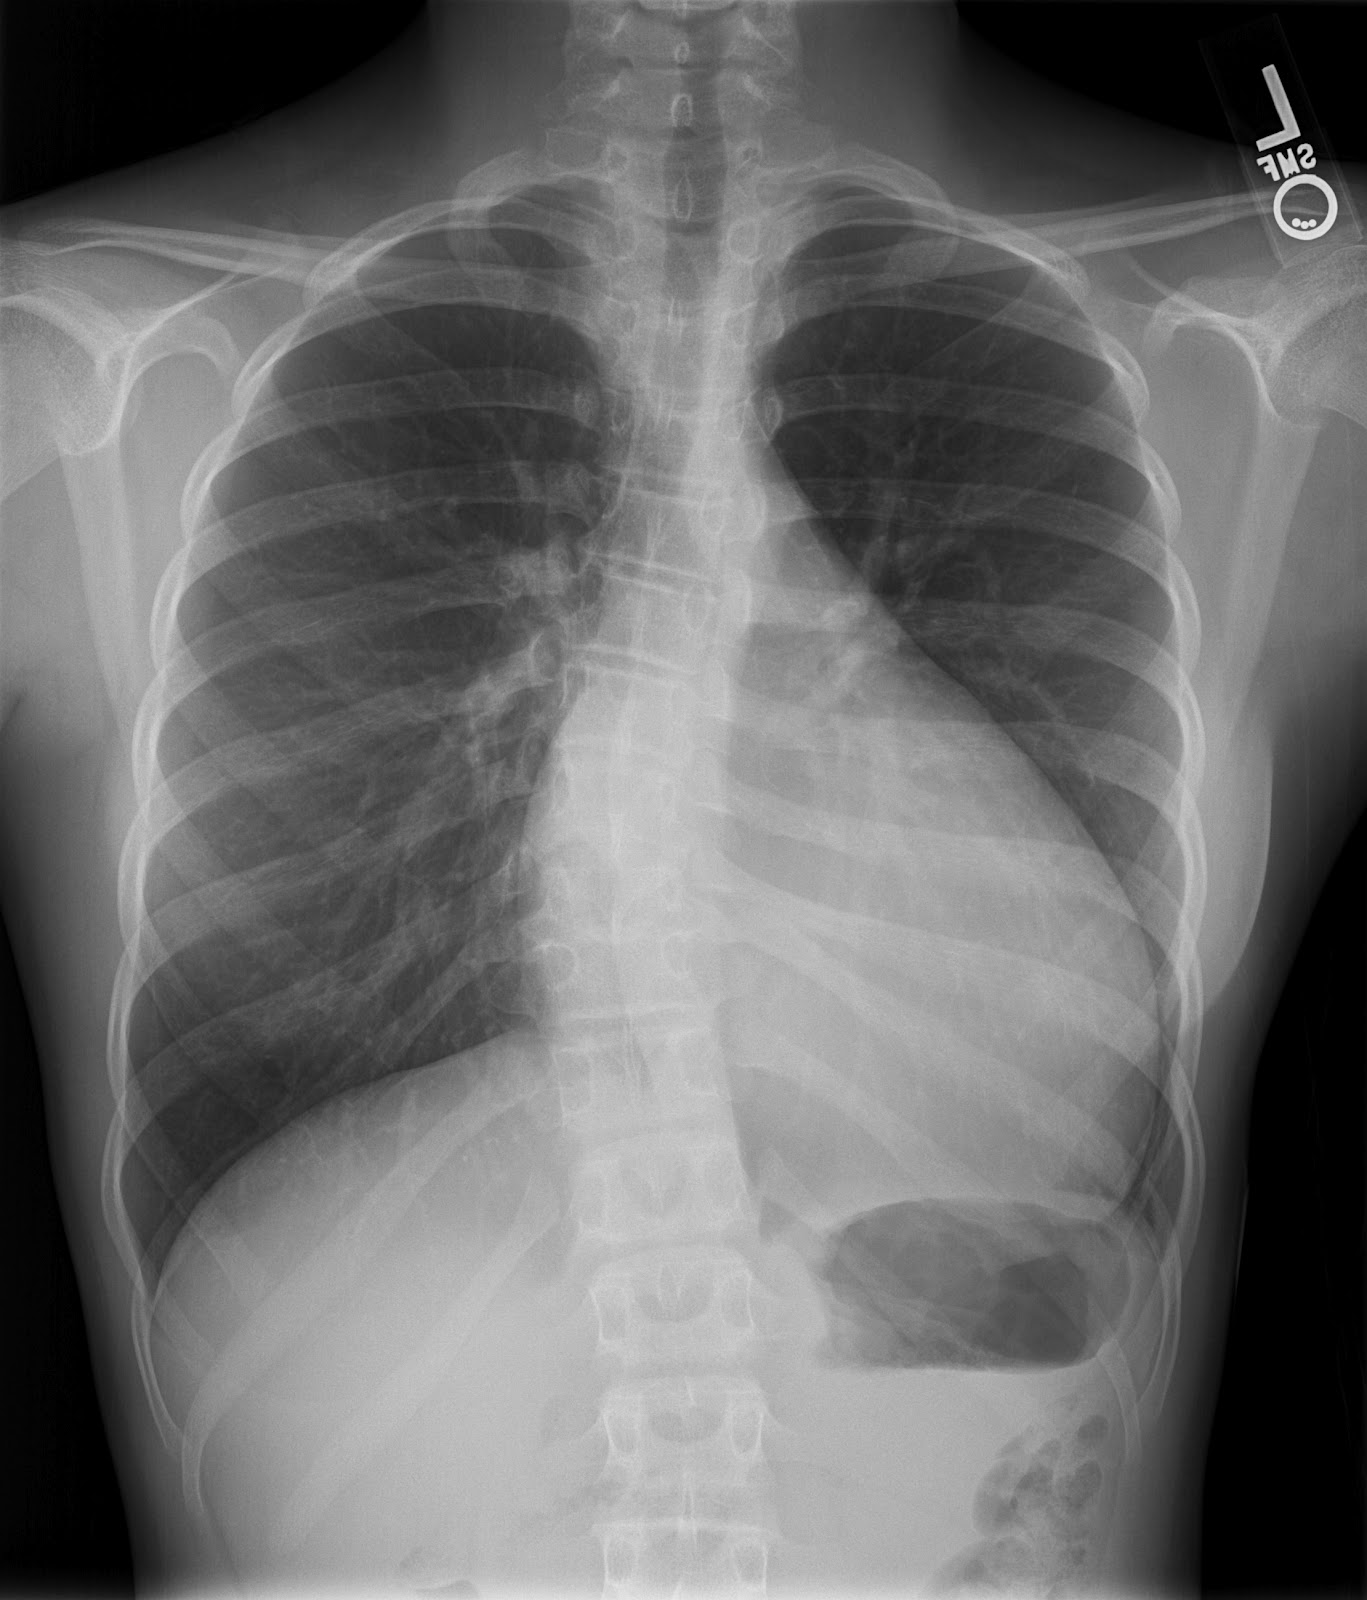

Pediatric Chest Pain Keys to the Diagnosis Consultant360

Pediatric Chest Pain Keys to the Diagnosis Consultant360 Define Chest Pain Exertional acute chest pain (acp) refers to pain/discomfort over the anterior thoracic region. angina pectoris is the medical term for chest pain or discomfort due to coronary heart disease. chest pain should be considered acute when it is new onset or involves a change in pattern, intensity, or duration. It's usually experienced when the heart works harder and. Define Chest Pain Exertional.